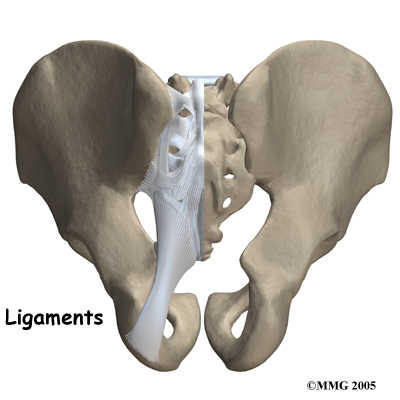

Several large, very strong ligaments hold the SI joint together. The strongest ligaments are in the back of the joint outside of the pelvis. The pelvis is a ring shape so these ligaments work somewhat like the hoops that hold a barrel together. The joint shape and the ligaments are one component in keeping the joint stable; the other component is the force of the muscles. If the ligaments are torn, the pelvis can become unstable.

This sometimes happens when a fracture of the pelvis occurs and the ligaments are also damaged. In most cases of injury to this joint, however, these ligaments are so strong that they are not completely torn unless a great amount of force is involved, such as in motor vehicle accidents.

When ligaments are injured or if they are lax due to hormonal changes (pregnancy) this decreases the stability of the SI joint. As this joint is normally a very stable joint, and requires stability to function, too much relative movement in the joint can cause significant pain and problems. The increased stretching of the abdominal muscles in pregnancy adds to the decreased stability of the joint as the muscles are unable to add as much force to compress the joint.